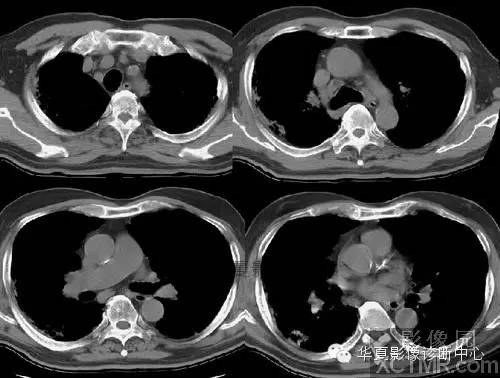

【病例】慢性嗜酸细胞性肺炎1例CT影像表现

CT图像特点:双侧胸膜下片状、蜂窝状改变,肺内长条索状影向胸膜延伸。

结果:慢性嗜酸细胞性肺炎

补充病例:

2006/04/24

2006/05/22